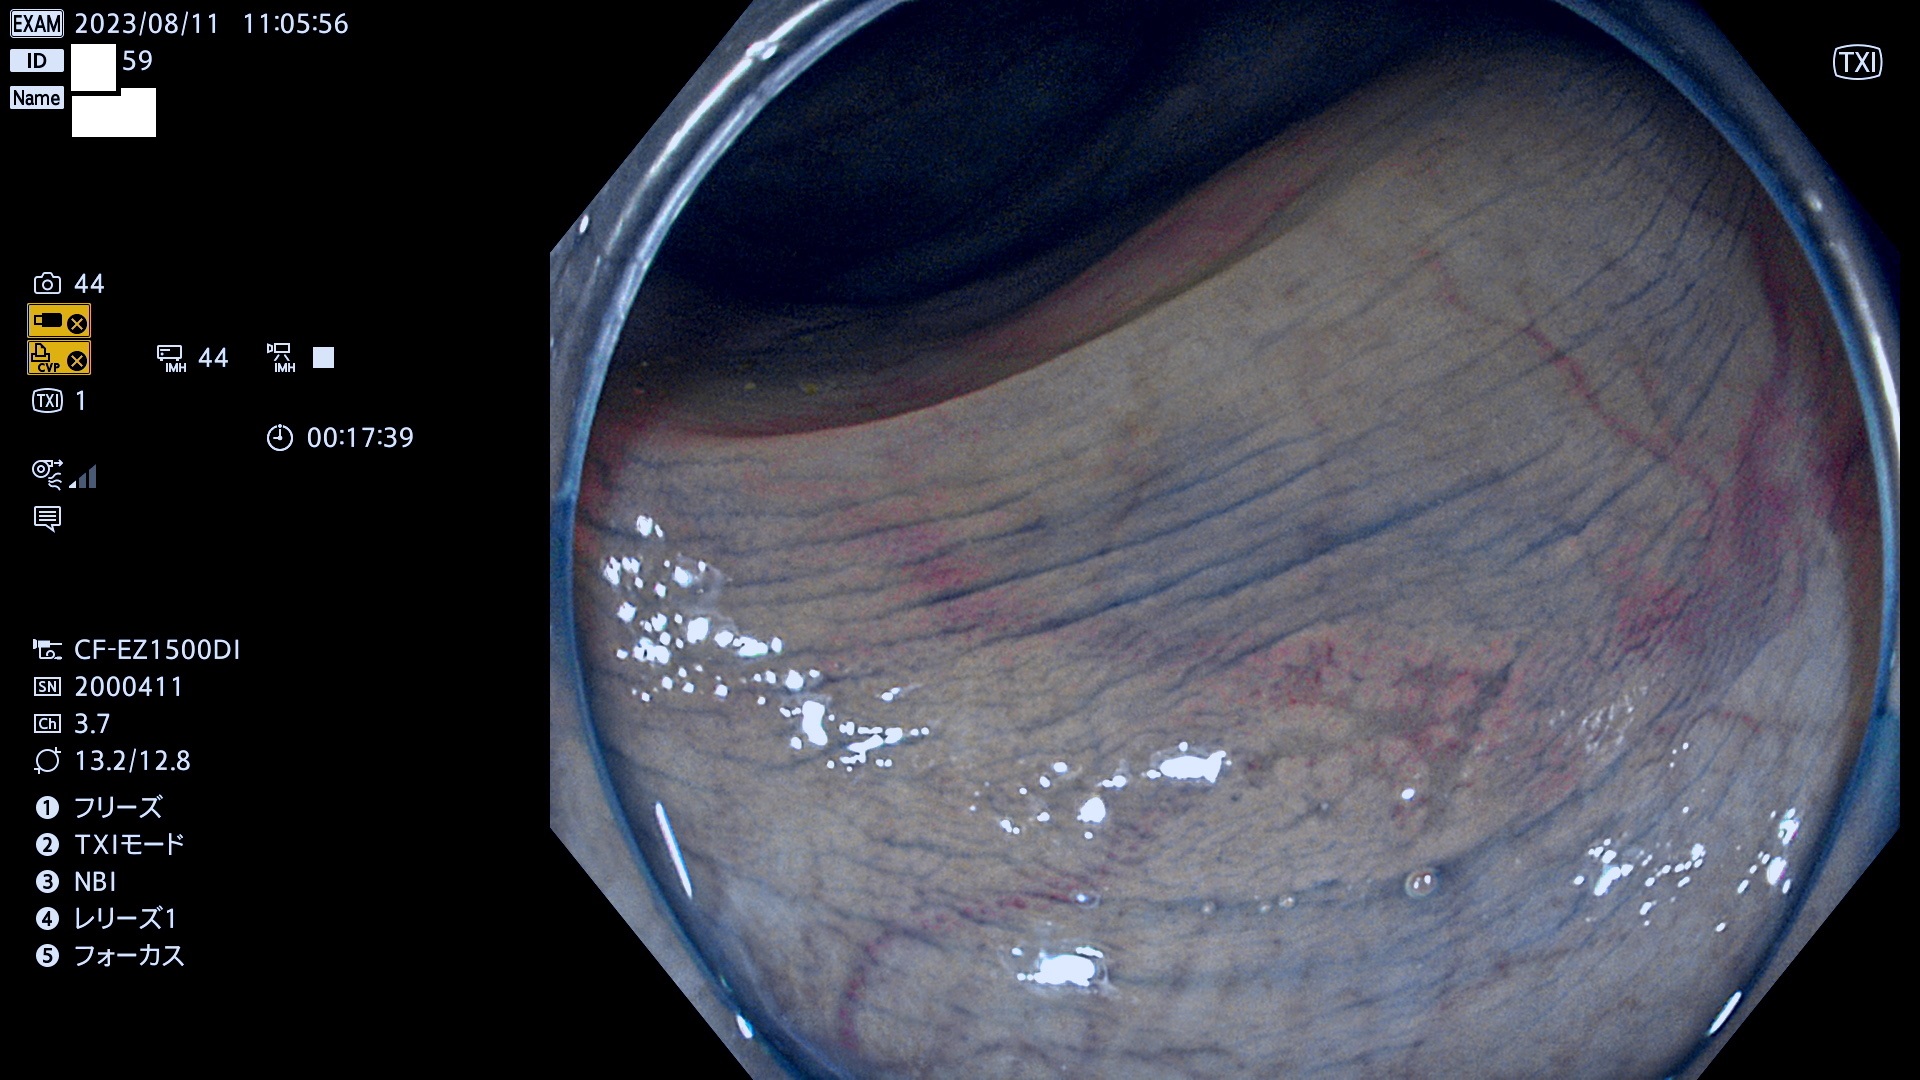

今週のUb、Uc型腺腫

表面型腺腫(Flat Adenoma)の中で、完全に平坦な物をUb、陥凹している物をUcと呼びます。平坦隆起型(Ua)よりも、発見が難しく危険な病変です。このタイプは「内視鏡後・大腸癌の重要犯人」であり、この発見率は「腺腫発見率」よりも、重要な意味があります。

毎週の検査(木・金・土・日)に発見されたUb、Uc型・腺腫を、その週の日曜の夜にUPし1週間、提示します。

抽出の対象期間 2023年8月10日(木)〜8月13(日)の4日間(48件の検査)11件